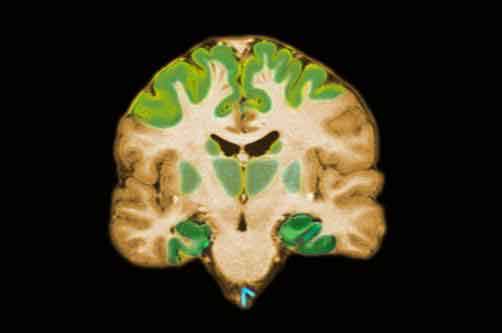

alzheimers_disease_brain

La prevenzione della salute cerebrale e, dunque, di malattie come l’Alzheimer passa anche attraverso un’alimentazione specifica che, in particolare, contrasti le alterazioni del metabolismo del rame, direttamente collegate all’insorgere della suddetta patologia.